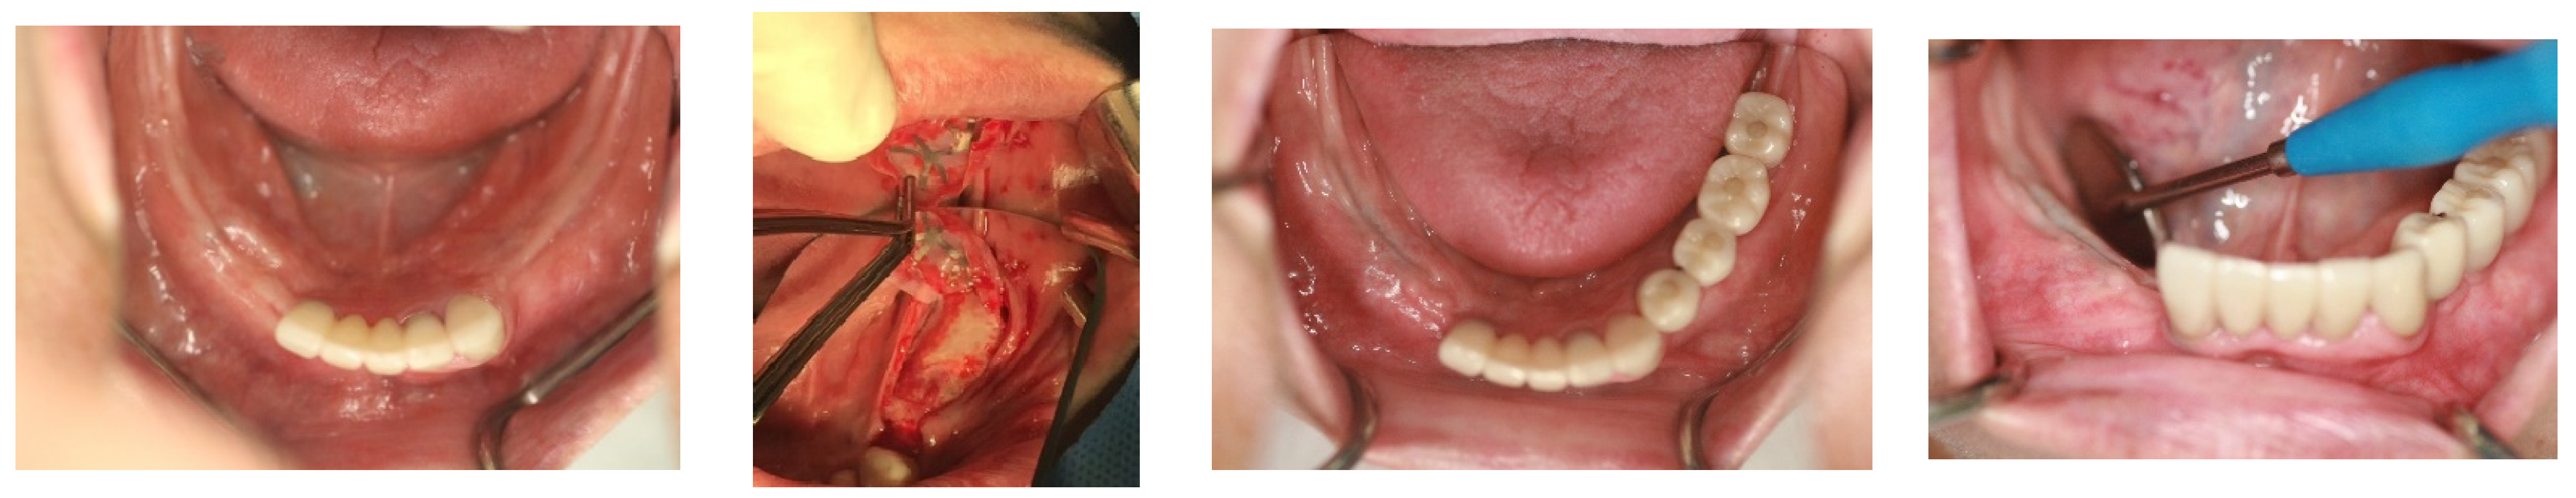

In April 2015, a 65-year-old female patient sought care at Purpose Driven Dental Clinic, reporting discomfort with her old upper and lower removable dentures. She had no medical history other than controlled hypertension, which was managed with medication. She had her lower posterior teeth extracted decades ago and had undergone several replacements of her removable dentures before visiting my clinic. Examination revealed severely atrophic upper and lower edentulous ridges, save for three remaining teeth (right upper canine, right upper incisor, and left lower canine). Panoramic X-ray imaging indicated that the residual crestal bone height in the first molar area above the upper border of the inferior mandibular canal was 2.2 mm on the right side and 4.0 mm on the left side. The patient expressed her desire for replacing the edentulous areas with fixed prostheses using dental implants (Figure 1).

Figure 1. The initial intraoral photos showed that the upper arch had only two teeth remaining, both with root caries and periapical abscesses, while the other teeth were missing. The lower arch displayed severely atrophic mandibular edentulous ridges, with only the left canine remaining. Please note that the residual crest of the right edentulous ridge is flush with the level of the mouth floor.